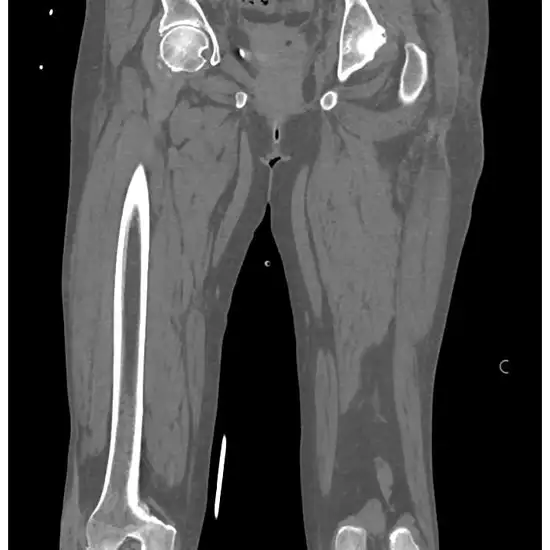

What is NCCT Left Thigh?

NCCT (Non-Contrast Computed Tomography) of the Left Thigh is a radiology procedure is used to diagnose the problems in the left thigh. The X-ray beam, the computer system is used to produce images of the bony structure of the thigh and its surrounding tissues.

This aids in diagnosing underlying problems such as thigh bone fracture, infection, injury, abnormal mass growth etc. It is also recommended if a patient is facing issues such as walking difficulty, swelling, inflammation pain etc.